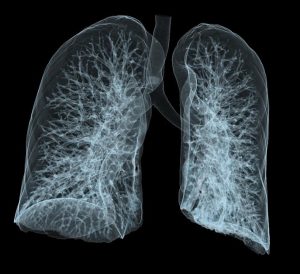

Přístrojové vybavení a ukázkové snímky:

- CT Siemens SOMATOM DEFINITION AS+ 128CT přístroj Somatom Definition AS+ značky Siemens umožňuje současné snímání 128 vrstev na jednu otočku rentgenky. Výjimečné prostorové rozlišení nabízí zobrazení tkáňových struktur od velikosti 0,24 mm, rozsah snímání obrazu 200 cm v kombinaci s tímto rozlišením zase umožňuje vyšetření celého těla pacienta během 10 vteřin. To je obzvlášť důležité při vyšetření pacientů s těžkými úrazy, v bezvědomí nebo u nespolupracujících pacientů. Tyto výjimečné parametry jsou využitelné zejména v traumatologii, kdy se jedná o co nejrychlejší stanovení diagnózy, a v kardiologii, kde umožňují vyšetření funkce srdce a hodnocení koronárních tepen včetně analýzy kalcifikací v jejich stěnách.Rychlost a kvalita obrazů je výhodná pro kvalitativní vaskulární diagnostiku a plánování intervenčních zákroků na cévách. Plně automatická funkce objemového zobrazení (3D) usnadňuje vyhodnocení prokrvení mozku. Snímky z tohoto přístroje jsou generovány ve formátu DICOM, což umožňuje jejich okamžité předání do systému PACS a prohlížení odeslaných CT obrazů na klinických pracovištích.